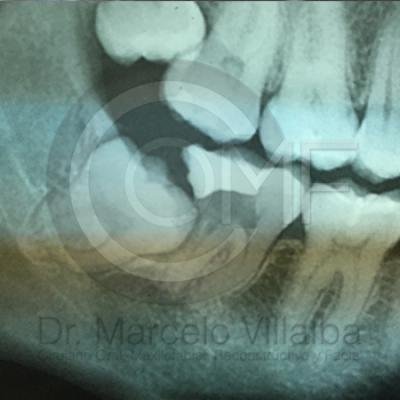

Generalmente en el momento de su erupción presentan procesos inflamatorios en la zona posterior de la cavidad oral, infección, dolor, movilidad de órganos dentarios, mal sabor en boca, mal olor en boca (halitosis), infección, incluso edema (aumento de volumen en tejido blando de la cara y/o boca) y complicaciones si no son atendidos. En el apoyo de diagnóstico se pueden requerir radiografías panorámicas y hasta tomografía en caso de ser necesarios.

Para el tratamiento de estas patologías se necesita en forma inicial estudios de laboratorio, radiografías o tomografías, estos estudios serán solicitados por el especialista a cada caso en particular, siendo su tratamiento quirúrgico bajo la modalidad de anestesia local o anestesia local más sedación consciente se puede realizar el procedimiento en corto tiempo y buen pronóstico.